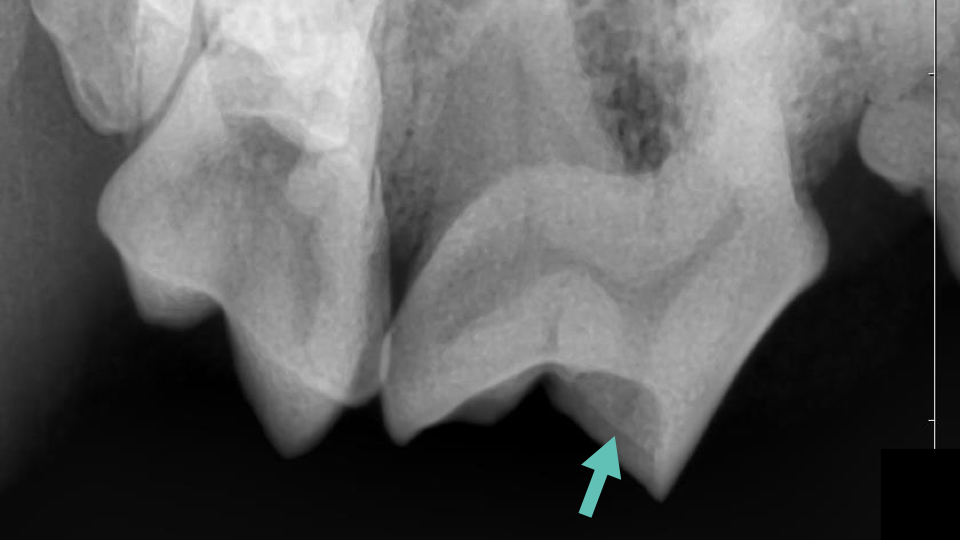

下の写真は第四前臼歯が折れてしまったわんちゃんです。

肉眼的には露髄しているかどうか判断が難しく、歯科レントゲンの撮影を行いました。

矢印で示した場所に象牙質が残っており、歯髄腔にギリギリ達していないと判断しました。

象牙質は再生するため露髄してから再生した可能性も否めませんが、根尖周囲病巣がないことを確認し神経を温存する治療を選択しました。